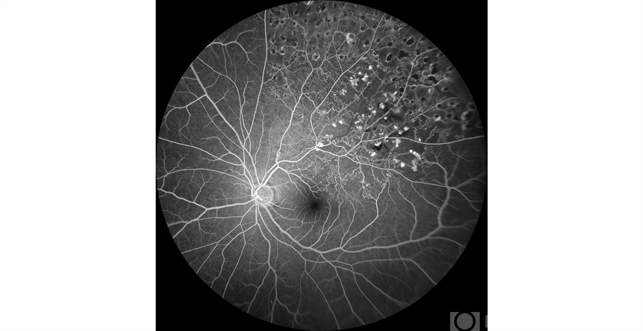

- branch retinal vein occlusion (BRVO), macular branch retinal vein occlusion (BRVO)

- Kristen Wagner, COT Tennessee Retina Nashville TN

Fundus camera

Clarus - Description

- Angiogram of a super temporal branch retinal vein occlusion on a 51-year-old male.